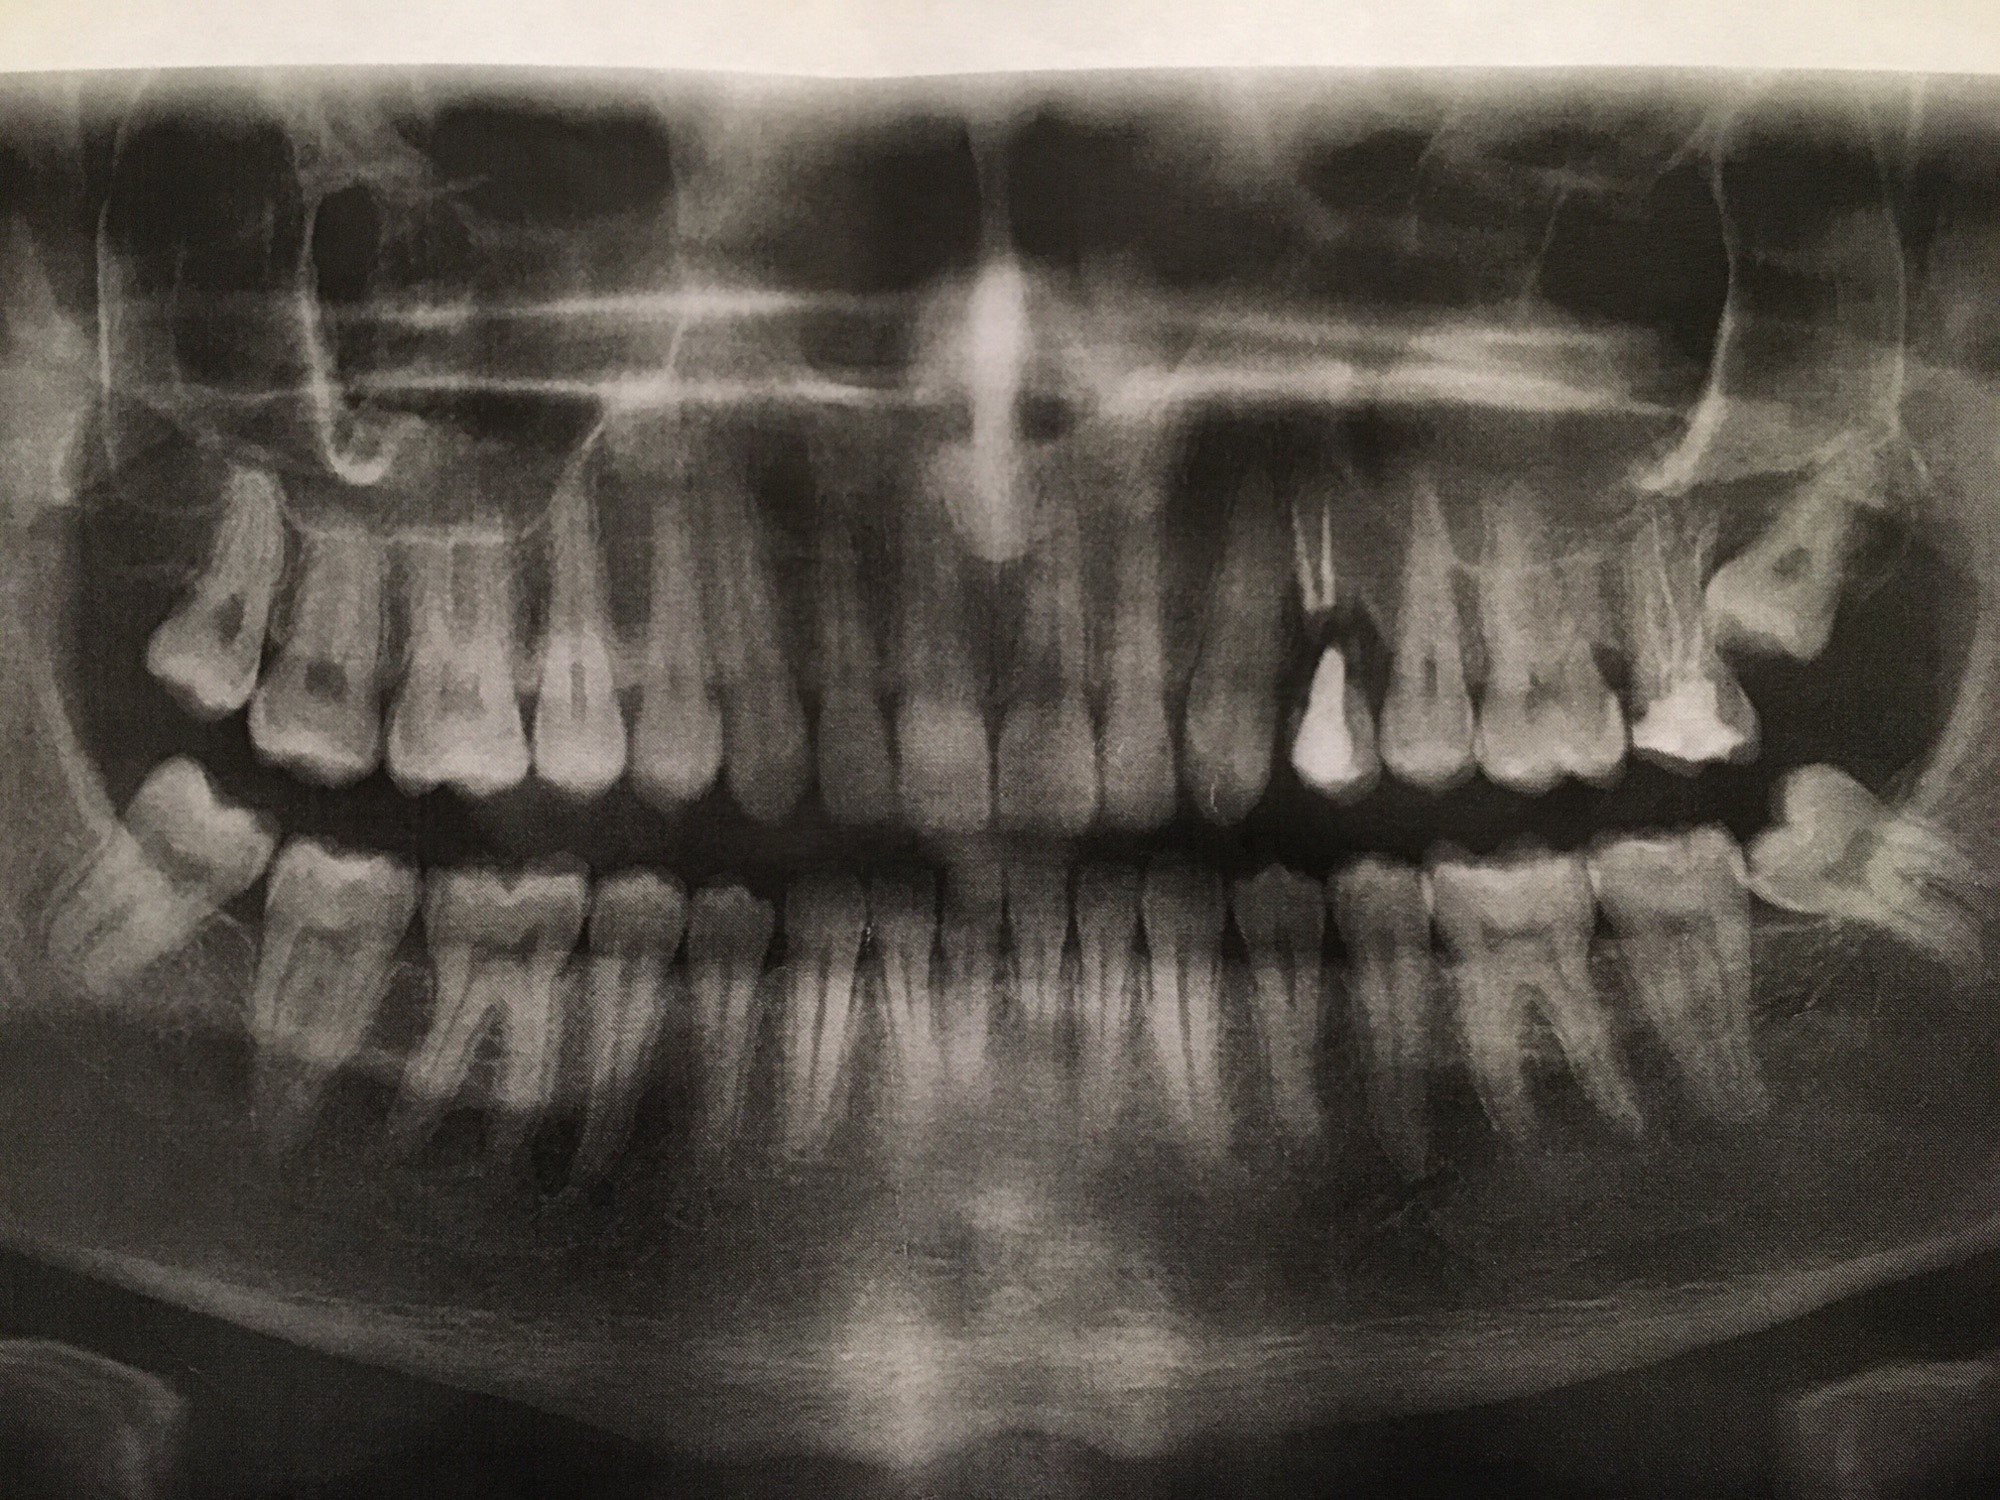

wie man an diesen bild sieht wachsen mir derzeit die weissheitszähne bzw sind schon teilweise draußen. Der zahnarzt meinte ich solle mir alle 4 weissheitszähne rausziehen lassen wobei mir die zähne auf der linken seite doch normal erscheinen.

Meine 2. sache wäre das wie man sieht auf der rechten seite oben ein zahn nur noch hängt. der ist auch wurzelbehandelt aber schon gebrochen wie man sieht, der wackelt auch und hängt eigentlich nur noch. wenn ich diesen ziehe lasse könnten sich dann die zähne von selber schließen bzw rutschen, also mit dem neuen weissheitszähn der da gerade ganz oben rechts wächst?

sieht sonst alles in ordnung aus? habe derzeit mega angst das ich noch weitere zähne verliere 🙁